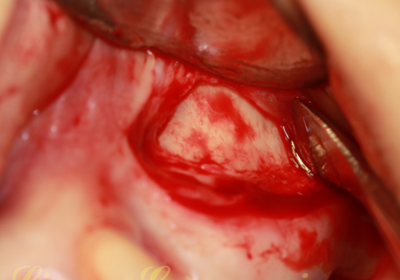

竇底骨量實在太有限,小于3mm骨高度,建議先提升植骨,二期種植。不種植就無需牙槽嵴頂切口、大翻瓣,頰側(cè)改良式切口:切口小,創(chuàng)傷小、術后反應輕。

開孔鉆配合停止環(huán),停止環(huán)從1mm逐漸增加,直到有落空感為止。連接水壓系統(tǒng),連接一次性注射器,1mm生理鹽水,橡皮堵緊緊堵住孔,輕壓將生理鹽水推入,在沒有開窗之前已經(jīng)將頰側(cè)上頜竇膜剝離